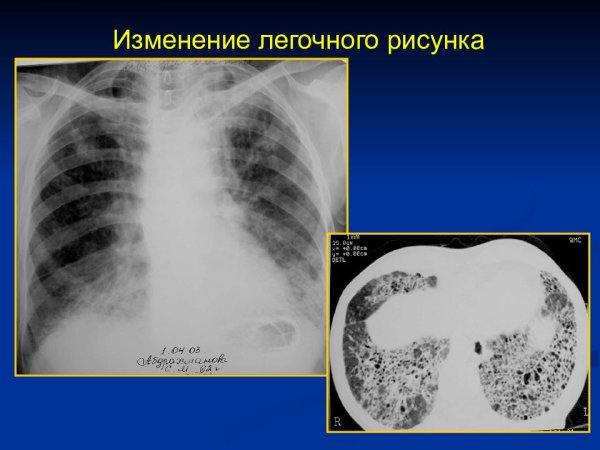

Изменение легочного рисунка – это понятие, которое относится к обнаружению и оценке изменений в структуре и паттерне легких на медицинских изображениях, таких как рентгеновские снимки или компьютерная томография. Легочный рисунок отражает состояние и функциональность легких, и его изменения могут быть связаны с различными заболеваниями и патологиями. Наблюдение и анализ изменений легочного рисунка помогает в диагностике и контроле этих состояний, что является важным инструментом в клинической практике. Детектирование и интерпретация этих изменений проводится специалистами радиологии и пульмонологии с использованием специального программного обеспечения для медицинского изображения. Все это позволяет более точно определить причину и характер изменений в легочном рисунке, а также вовремя начать необходимое лечение и наблюдение за пациентом.